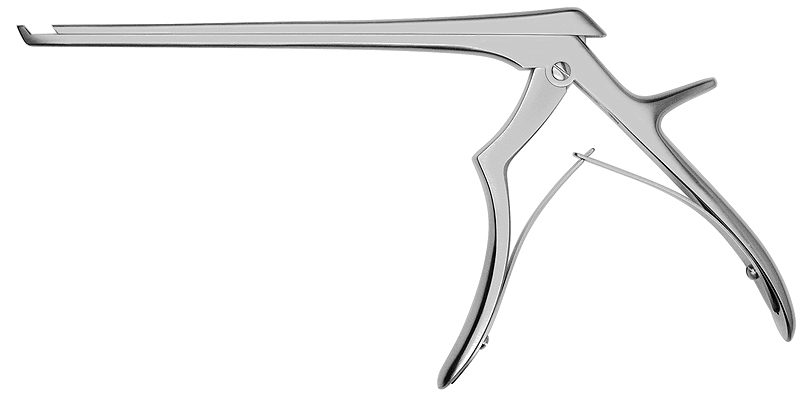

Kềm gặm xương (ronguer)

Kềm có mỏ bén, khép chặt lại khi tay bóp cán kềm. Trên cán kềm có thanh đàn hồi nên khi buông lỏng tay thì kềm sẽ mở ra. Đặc điểm này giúp các phẫu thuật viên dễ dàng lặp lại các động tác gặm xương mà không cần tốn sức để mở kềm ra sau khi bóp. Phần mỏ kềm có thiết kế lõm hướng về phía trong, có thể chứa 1 ít xương sau khi gặm.

Kềm gặm xương không được dùng để nhổ răng, vì mỏ kềm được thiết kế nhằm để cắt hơn là để ôm lấy răng, dùng sai sẽ gây mòn kềm.

Kềm gặm xương cũng khá là mắc tiền, nên chú ý cẩn thận khi sử dụng. 1 loại kềm gặm xương hay gặp khác là kềm Kerrison, chủ yếu được sử dụng trong nâng xoang cửa sổ (nâng xoang hở).